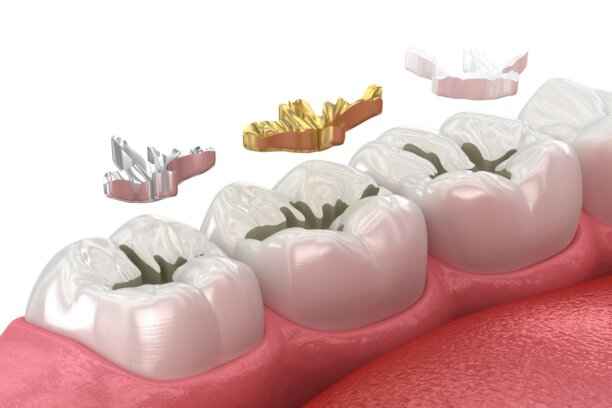

3- حشو Inlay or Onlay

تُعتبر حشوات Inlay وOnlay من الحلول المتقدمة التي تقع بين الحشو التقليدي والتلبيسة الكاملة. تُصنع عادة في المختبر من البورسلان أو مواد عالية الجودة، ويُحدد سعر حشو اسنان هنا بناءً على دقة التصنيع ونوع المادة.

☆ ما هو الفرق بين Inlay و Onlay؟

- Inlay: يُستخدم عندما يكون التسوس داخل حدود سطح السن دون تغطية النتوءات.

- Onlay: يغطي جزءًا أكبر من السن، وقد يشمل نتوءًا أو أكثر، ويُستخدم في الحالات الأوسع.

☆ مميزات Inlay و Onlay

- قوة ومتانة عالية تدوم لسنوات طويلة.

- مظهر جمالي ممتاز خاصة عند استخدام البورسلان.

- حماية أفضل لبنية السن مقارنة بالحشوات التقليدية.

- مقاومة عالية للتآكل والتصبغات.

- ملاءمة دقيقة تقلل من احتمالية تسرب البكتيريا.

ما هي أنواع حشو الأسنان واسعارها؟

تتنوع مواد الحشو المتاحة في العيادات الحديثة، ولكل نوع خصائصه وسعره التقريبي داخل السعودية:

☆ حشو الكومبوزيت (الراتنجي التجميلي):

- السعر: من 250 إلى 500 ريال سعودي للسن الواحد

- مناسب للأسنان الأمامية والخلفية

☆ الحشو المعدني (الأملغم):

- السعر: من 150 إلى 300 ريال سعودي

- يُستخدم غالبًا في الأضراس الخلفية

☆ حشوات Inlay وOnlay الخزفية:

- السعر: من 800 إلى 1500 ريال سعودي

- تُصنع في المختبر بدقة عالية

☆ الحشو الزجاجي (Glass Ionomer):

- السعر: من 200 إلى 400 ريال سعودي

- مناسب للأطفال وحالات التسوس البسيطة

ويختلف سعر حشو اسنان تبعًا لعدد الأسطح المعالجة وحجم التلف.